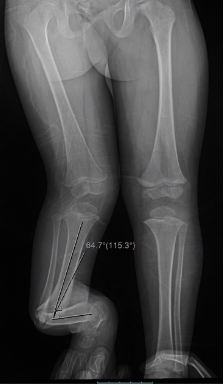

El tratamiento de la Pseudoartrosis Congénita de Tibia y Peroné (PCTyP) ha sido diverso. Todas las técnicas de tratamiento tienen una cuota de complicaciones, pero es la re-fractura y la falta de unión las principales consecuencias que se desean evitar. El objetivo de esta investigación se basa en analizar las técnicas quirúrgicas empleadas en nuestro centro y determinar los resultados. Se realizó un estudio retrospectivo, donde se estudiaron 11 pacientes con esta enfermedad con un seguimiento promedio de 4,73 años (DS±4,56). Todos los pacientes en quienes se utilizó la técnica de Charnley-Williams (CW) lograron la consolidación, la protección del clavo funcionó hasta que el extremo proximal de la tibia queda desprotegido al crecer el hueso y se produjeron angulaciones en esta zona, usualmente en la tibia proximal. Con el uso del clavo endomedular (EM) telescópico de Fassier-Duval (FD) se logra la protección de todo el hueso, inclusive durante el crecimiento. Se concluye que la técnica de CW es un buen método para la resolución de esta enfermedad y con el uso del clavo EM de FD se evita la refractura y se logra la unión permanente a medida que continúa el crecimiento del hueso. La discrepancia de los miembros inferiores es debida a la afectación de la tibia que compromete su crecimiento normal.